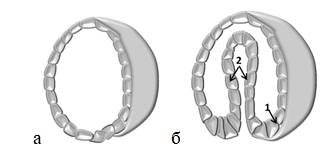

На четвертой неделе эмбрион превращается в однослойный пузырек -бластоцисту (рис. 1 а), часть стенки которого, впячиваясь внутрь, образует внутренний слой. Процесс образования двухслойного пузырька называется гаструляцией, эмбрион на этой стадии – гаструлой (рис. 1 б), а его листки: экто- и эндодермой. Они являются зачатками органов и тканей плода. Позже между ними возникает третий (средний) слой – мезодерма.

Рисунок 1. Эмбрион на стадии бластоцисты (а) и гаструлы (б): 1 – эктодерма, 2 – эндодерма

Из эндодермы впоследствии будут формироваться органы дыхания и пищеварения; из мезодермы – скелет, мышцы, почек, кровеносные сосуды и сердце; из внешнего листка (эктодермы) – кожа, волосы, глаза, зубная эмаль и нервная система ребенка.